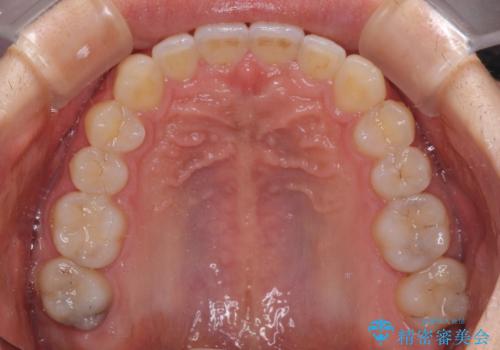

- 口元の突出感を治したいとのことで来院された患者様です。

上下顎ともにIPR(歯と歯の間を削る)と歯列全体の拡大によって口元が引っ込むように設計し、インビザラインにより治療を行うこととしました。

抜歯をして口元を下げなければならないほど出っ歯ではなかったため、少しずつ治療ゴールを変更しながら仕上げていきました。

気になっていた前歯の飛び出した印象は、最終的にはスッキリと引っ込み、大変満足していただきました。